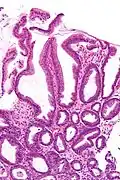

| Micrograph of a reactive gastropathy. H&E stain. | |

- Foveolar hyperplasia (black arrow), as a tortuosity in the "neck" region of the gastric glands.

- Scant or minimal inflammatory cells (white arrow), i.e. lack of large numbers of neutrophils and plasma cells..

- Smooth muscle hyperplasia in the lamina propria (in black oval).

The diagnosis is by examination of tissue, e.g. a stomach biopsy.

Low mag. -